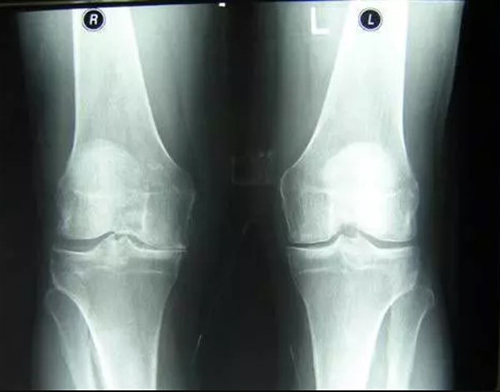

สาเหตุหลักของโรคข้อ คือการตกตะกอนของผลึกเกลือในข้อ เนื่องจากระบบไหลเวียนโลหิตและของเหลวไขข้อ (synovial fluid) เสื่อมลง:

- กรดยูริก (Urate crystals) ทำให้เกิดโรคเกาต์

- แคลเซียมเกาะกระดูก (Osteophytes) คือตัวการของโรคข้อและกระดูกกว่า 97% เช่น โรคข้ออักเสบ โรคข้อเสื่อม โรคกระดูกอ่อน โรคกระดูกพรุน โรคไขข้ออักเสบ โรคถุงน้ำในข้ออักเสบ และแม้แต่ซีสต์ของปมประสาท

เมื่อเกลือเหล่านี้เกาะอยู่บนพื้นผิวของข้อต่อ คราบเกลือเหล่านี้เหมือนกระดาษทรายที่ทำลายเนื้อเยื่อรอบโดยรอบ กระดูก และกระดูกอ่อน เมื่อผลึกโตขึ้น เกลือจะเริ่มทำลายเนื้อเยื่อของกล้ามเนื้อ เอ็น หลอดเลือด และเส้นเลือดฝอย ทำให้เกิดการอักเสบ ติดเชื้อ บวม ก่อให้เกิดการอักเสบและปวดอย่างรุนแรง

ในกรณีรุนแรง การสะสมเกลือจำนวนมากอาจทำให้กระดูกหักได้ง่ายเมื่อมีการเคลื่อนไหวอย่างกะทันหัน ส่งผลให้พิการและข้อต่อไม่สามารถเคลื่อนไหวได้